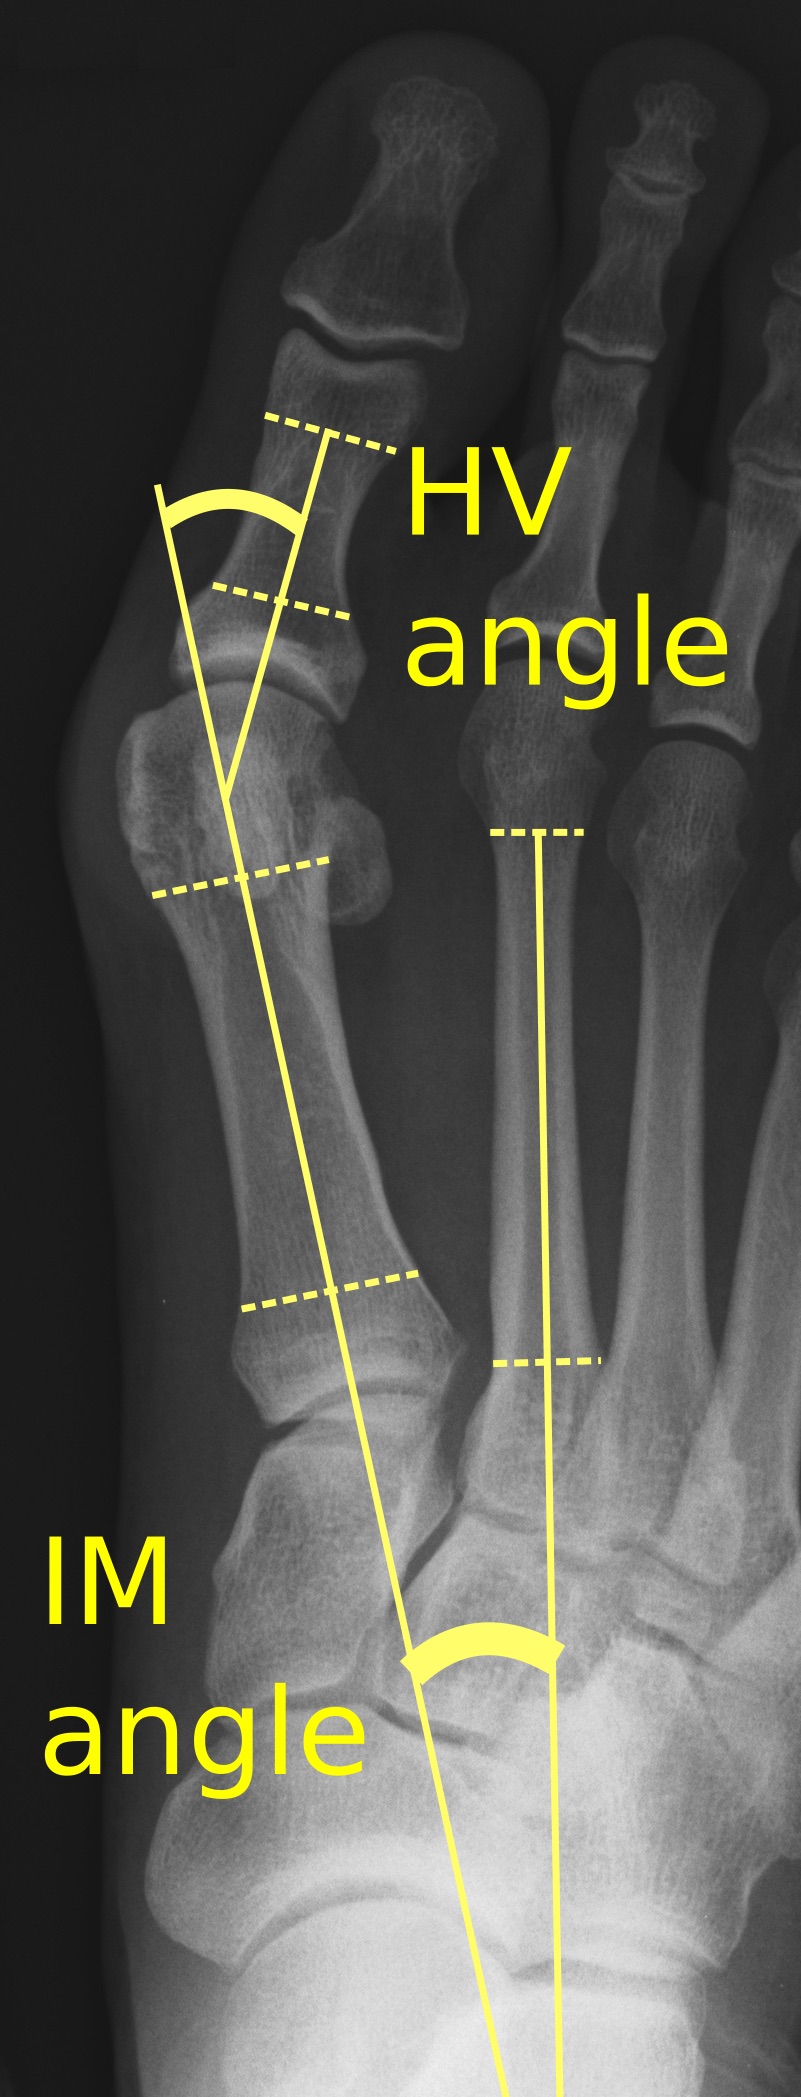

무지외반증은 체중 부하 상태에서 촬영한 단순 X-선 촬영을 통해 진단하고 분석할 수 있다.[10] '무지 외반 각도'(Hallux Valgus Angle, HVA)는 엄지발가락의 근위 지골과 첫 번째 중족골의 장축 사이의 각도이며, 15–18°보다 큰 경우 비정상으로 간주된다.[11]

무지 외반 각도(HVA)에 따른 무지외반증 심각도 분류[12]

- 경도: 15–20°

- 중등도: 21–39°

- 중증: ≥ 40°

'중족골 간 각도'(Intermetatarsal Angle, IMA)는 첫 번째와 두 번째 중족골의 종축 사이의 각도이며, 일반적으로 9° 미만이다.[11]

중족골 간 각도(IMA)에 따른 무지외반증 심각도 분류[12]

- 경도: 9–11°

- 중등도: 12–17°

- 중증: ≥ 18°